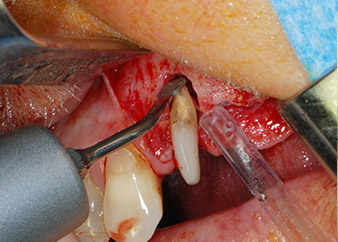

Un mese più tardi, nel giorno programmato per l'intervento, il dolore e l'infiammazione in corrispondenza del dente 24 erano minimi, ma era ancora presente mobilità di classe 2 secondo Miller. Dopo l'apertura dei lembi e la pulizia del tessuto periapicale e periradicolare infetto, l'estensione della mancanza ossea si è resa evidente (Figg. 2 e 3).

Tutto il tessuto osseo vestibolare e distale era mancante in corrispondenza della radice buccale. La possibilità di attacco era essenzialmente ristretta alla radice palatale, evidenziando la prognosi negativa preliminare. Anche il dente 27 mostrava un punto di attacco orizzontale ridotto e una rarefazione apicale minima (cfr. Fig. 1), senza sintomi clinici.

Si è mantenuta , tuttavia, l'idea iniziale di conservare entrambi i denti come appoggi temporanei del ponte durante il periodo di sei mesi per l'osteointegrazione degli impianti. In seguito la situazione si sarebbe assestata. In primo luogo, in un tentativo di risolvere il problema entro-periodontale, la superficie radicolare rimanente è stata attentamente sbrigliata con apparecchiatura piezoelettrica (Piezomed di W&H con l'attacco S1 a spatola, progettato in origine per l'erosione della parete laterale del seno mascellare) Fig. 4).